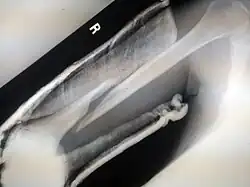

Internal and external views of an arm with a compound fracture, both before and after surgery

A bone fracture (abbreviated FRX or Fx, Fx, or #) is a medical condition in which there is a partial or complete break in the continuity of any bone in the body. In more severe cases, the bone may be broken into several fragments, known as a comminuted fracture.[1] An open fracture (or compound fracture) is a bone fracture where the broken bone breaks through the skin.[2]